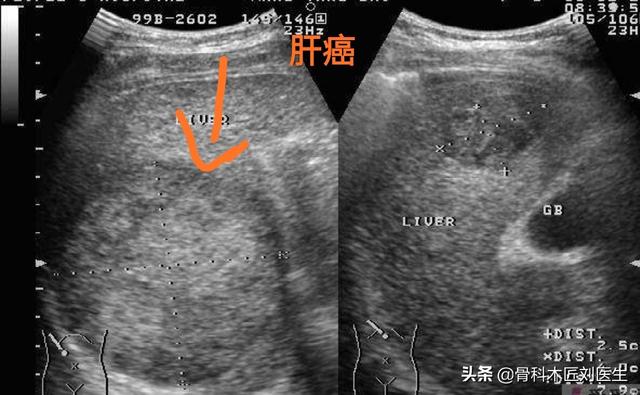

- Tout d'abord, pour le dépistage du cancer du foie, je recommande de combiner l'échographie et l'alpha-fœtoprotéine, car l'échographie permet de détecter clairement les tumeurs hépatiques de plus d'un centimètre et l'alpha-fœtoprotéine, en tant que marqueur tumoral du cancer du foie, accroît fortement la précision du diagnostic du cancer du foie.

- Si une échographie du foie ne révèle pas de tumeur dans le foie, ou si la nature de la tumeur ne peut être déterminée, une alpha-fœtoprotéine élevée est hautement suspecte de la présence possible d'un carcinome hépatocellulaire.Une tomodensitométrie du foie peut être réalisée.Je recommanderais d'emblée une tomodensitométrie améliorée du foie, car cette technique est relativement efficace pour identifier les tumeurs hépatiques.